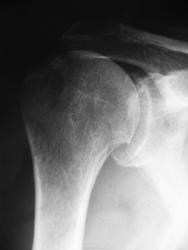

Пациент около 70 лет обратился с жалобами на боли в правом плечевом суставе, повышение температуры до 38-39 градусов в конце января, травмы не было:

Госпитализирован, установлен диагноз гнойного артрита, проведена артротомия, дренирование, согласно выписке на рентгенограммах (через неделю) выявлена перестройка костной структуры, без вынесения диагноза:

В настоящее время периодически субфебрильная температура, умеренные боли, ограничение движений. Сегодняшние снимки

Ести ли признаки остеомиелита или это просто участок остеопороза? Размеры его в динамике как будто увеличиваются.

//Ести ли признаки остеомиелита или это просто участок остеопороза? //

Я не вижу, и даже не могу понять, что вы имеете в виду. Может обведете?

Гнойный артрит плечевого сустава! Да тут все м.б. и остеомиелит не исключен, а может он и первый.

Первый снимок (2643 1 и 2) в конце января, второй (2642)- сегодня.

Не очень убедительно. Тем более, что эта область находится вне сустава. До тех пор, пока цел кортикал, все это "вилами по воде". Выбор за вами: можете написать "можно думать, нельзя исключить", можете доснять другую сторону.

На мой взгляд, изменения больше касаются не головки плечевой кости, а задней части суставной поверхности лопатки и суставной поверхности ключицы в ключично-акромиальном сочленении. Здесь мне видится неровность, нечеткость и узурация субхондральногоо слоя.

Попала инфекция, развился гнойный артрит плечевого и ключично-акромиального суставов. Рентгеновская картина, как и положено, отстает от клиники.

Насчёт лопатки поддерживаю. В головке плеча этот участок повышенной прозрачности тем более в 70 не патология

на мой взгляд дегенеративно-дистрофические изменения в суставе с костях его образующих

Но ведь клиника гнойного артрита. Были проведены артротомия и дренирование.